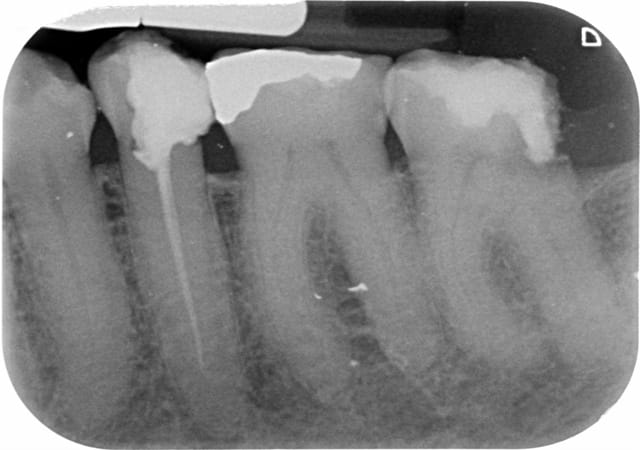

Une patiente de 71 ans, suivi depuis longtemps au cabinet par mon prédécesseur, se présente au cabinet pour une visite de contrôle. Je découvre en plus de 26 à extraire, une carie profonde en D de 37 ainsi qu'un traitement insuffisant sur 35. 35 et 37 devant être couronnées. Après ce 1er RDV, 2 rendez-vous sont pris pour réaliser d'abord le retraitement sur 35 puis l'endo sur 37.

Sachant qu'en plus le retraitement de 35 ainsi que le traitement de 37 ne va pas complètement à l'apex radiologiquement (mais avec le localisateur j'y suis).

L'obturation provisoire de la 47 n'a pas l'air étanche en distal.